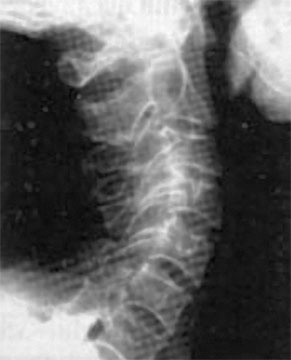

Вторит ему Говард Лэнгстайн (Howard Langstein), руководитель службы пластической и реконструктивной хирургии в университетской клинике: «Резорбция костной массы приводит к потере былой четкости овала и к провисанию мягких тканей. Внешне это проявляется в том, что нижняя часть лица приобретает более мягкие овальные очертания, снижается тонус кожи щек, подбородка и шеи, в результате чего очертания лица приобретают характерный возрастной вид». Далее Г. Лэнгстайн заявил: «Хотя врачи всегда знали, что кости со временем меняются, но как это проявляется с возрастом – не оценили». В свою очередь остеопороз черепа напрямую зависит от кровоснабжения головы. И мы опять приходим к неизбежности хорошего состояния «трубопроводов», несущих питание к мозгу и лицу. А перекрываться это питание может не только из-за сжатия артерий, но и всех сосудов шейного отдела, в том числе и вен. В этом случае артериальная кровь будет поступать, а отток будет заблокирован, что вызовет повышение внутричерепного давления и сильную головную боль. Головной мозг снабжается из двух сосудистых бассейнов. Первый составляют сонные артерии. Поражение этих артерий часто приводит к развитию острого нарушения мозгового кровообращения (инсультам). Ко второму относятся правая и левая позвоночные артерии. Их поражение не приводит к таким тяжелым осложнениям, как инсульт, но может способствовать головокружениям, усиливающимся при движениях головы или изменении положения тела. Подобные симптомы могут вызываться спазмами как позвонков, так и мышц шеи. К примеру, перенапряжение затылочных мышц зачастую ведет к головным болям и к проблемам со зрением. Так что шейный отдел позвоночника, состоящий из 7 позвонков, должен иметь и достаточную длину, и определенную статику (рис. 67). ![]() Рис. 67. Нормальная статика шеи. Правильный физиологический изгиб: А=А1 А что в действительности имеем мы? Обычно, даже при здоровом позвоночнике (только где его найдешь?), он начинает с возрастом деформироваться, «проседать», менять статику. Появляется симптом смещенной вперед и запрокинутой назад головы (рис. 68). ![]() Рис. 68. Гиперлордоз шейного отдела позвоночника: B > B1 В результате небольшой физиологический изгиб гипертрофируется, что ведет к проваливанию шейных позвонков вглубь шеи, особенно интенсивно при «сидячей» работе. Формируется гиперлордоз шейного отдела позвоночника. Чаще всего виной тому является не возраст, не тяжесть гравитации, а элементарно наша плохая осанка: сутулость, неправильная статика шеи, опущенная вниз голова, когда попытка смотреть в глаза собеседника достигается взглядом исподлобья за счет запрокидывания головы назад. Посмотришь на лицо, вроде бы женщина еще молодая, ухаживающая за собой. А взглянешь со стороны – прямо старушка ковыляет – ссутулилась, шейка вперед подалась, плечики сжались. Хорошо, сама себя не видит, а то бы очень огорчилась. Из-за того, что с возрастом диски между позвонками уплощаются, длина шеи укорачивается и частенько весьма значительно (рис. 69). ![]() Рис. 69. Шейный отдел позвоночника Появление поперечных морщин и складок на боковой поверхности шеи служит точной приметой этого явления. Проведите тесты – проверьте свою шею на ее статику – физиологический изгиб. Вот тут вам и пригодится второе зеркальце. 1. Возьмите его и внимательно рассмотрите свою шею в профиль и особенно сзади, приподняв волосы. Не стоит удивляться тому, что, возможно, там вы ее вообще не найдете – слишком коротким будет расстояние от первого позвонка до последнего – 7-го шейного, который легко прощупывается. В идеале длина шеи должна быть одинаковой по всей ее окружности. Если вам больше 40 лет, будьте готовы к тому, что, измерив свою шею, вы найдете сзади не более 2–3 см своей шеи. 2. Если запрокинуть голову назад, появляется ощущение, что в основание головы упирается кол – это ваш 7-й позвонок упирается в первый. Закономерно напрашивается вопрос: «А куда делись оставшиеся 5?» – запали внутрь шеи. И как бы ни было ухожено лицо, ни о какой молодости говорить уже не приходится. 3. Сравните длину вашей шеи с «эталонной». Похоже? Или…? Скорее всего или… Чтобы восстановить свою шею, недостаточно лишь массажами убрать жир с так называемой «холки» (кстати, основная часть этого горбика не жир, а отек лимфы) и «разбить остеохондрозные соли». В первую очередь необходимо восстановить статику шейного отдела. Ведь не «вытащив» запавшие вглубь шеи позвонки, характеризующие гиперлордоз шеи, вам никогда не приобрести четкого овала. При этом проблемы статики шейного отдела не ограничиваются возрастным гиперлордозом шейного отдела, когда шейные позвонки проваливаются вглубь шеи (рис. 70). Частенько, наоборот, этот изгиб может быть и излишне спрямлен (рис. 71). ![]() Рис. 70. Гиперлордоз шейного отдела ![]() Рис. 71. Спрямление шейного отдела позвоночника А вот для молодого поколения, особенно в наше время тотальной компьютеризации, характерен третий дефект неправильной статики шеи, который я назвала «компьютерной шеей» (рис. 72). Провоцируясь в большей степени именно вытягиванием шеи к экрану монитора, он выражается в ее вытянутости вперед и тоже сопровождается избыточным грудным кифозом – сутулой осанкой. ![]() Рис. 72. «Компьютерная» посадка шеи При такой статике центр тяжести головы (ЦТ) смещен вперед относительно центра тяжести тела (рис. 73). |